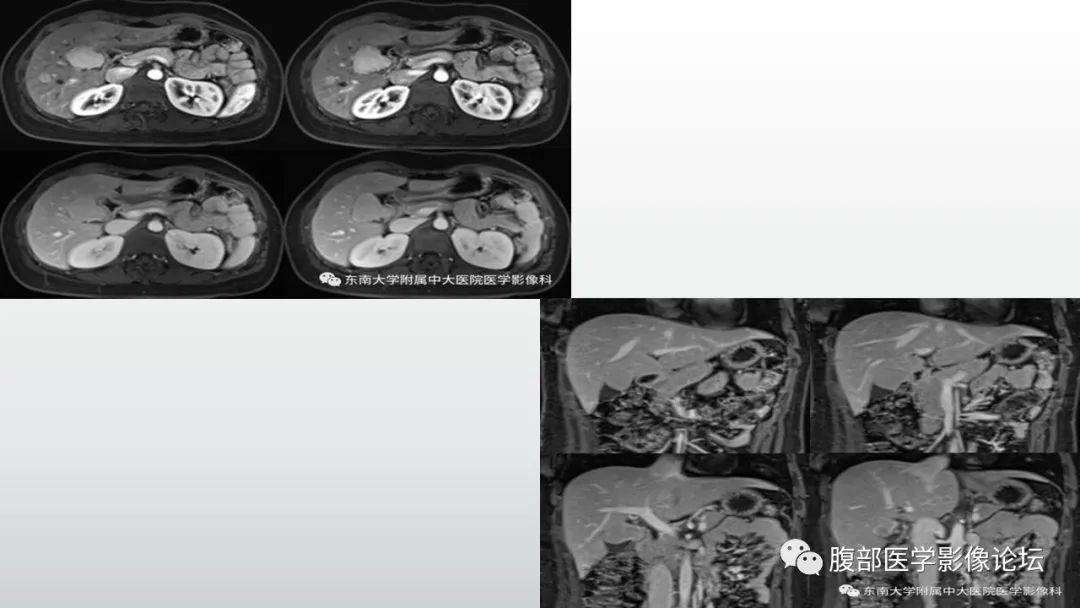

【病例】胆囊管状腺瘤1例CT及MR影像表现-1

【病例】胆囊管状腺瘤1例CT及MR影像表现-2